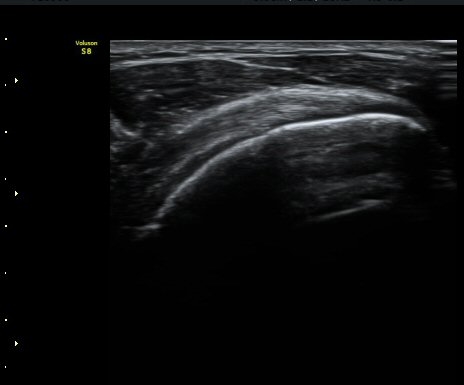

¾î±ú ¾Õ À̵ιڱ٠Ⱦ´Ü¸é°Ë»ç¿¡¼­ ÀÌºÎ¹Ú±Ù°Ç °í¶û ¾Æ·¡ ºÎÀ§¿¡¼­ À̵ιڱ٠ÀåµÎ ÁÖÀ§¿¡

¼ö¾×Àú·ù°¡ °üÂûµÈ´Ù(±×¸² 1, 2). °ß°©ÇÏ±Ù°Ç Á¾´Ü¸é°Ë»ç¿¡¼­ °ß°©ÇϱٰÇÀÇ °üÀý³»ºÎÀ§(±×¸² 3)